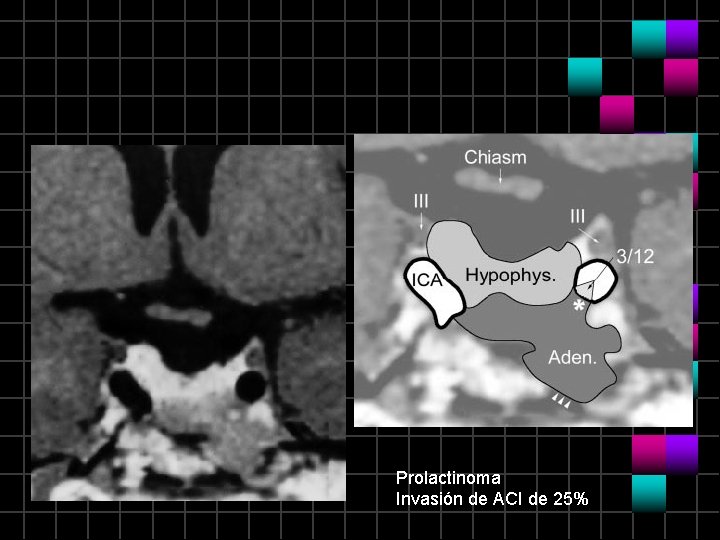

Prolactinoma

Prolactinoma Invasión de ACI de 25%